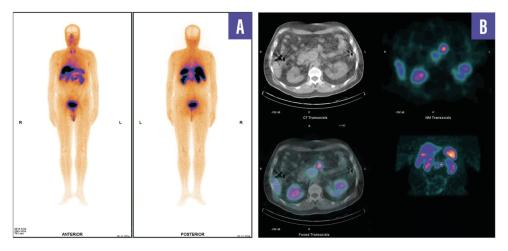

Un homme de 53 ans, sans antécédents, consulte pour des douleurs abdominales diffuses évoluant depuis plusieurs semaines. Le bilan biologique est normal. Une tomodensitométrie abdomino-pelvienne met en évidence une masse rétropéritonéale infiltrante associée à une adénopathie lombo-aortique. La tomographie par émission de positons (TEP-TDM au 18F-FDG) montre un hypermétabolisme léger de la lésion rétropéritonéale, mais l’adénopathie ne fixe pas le FDG (fig. 1). Un foyer hypermétabolique thyroïdien droit est également détecté. Une biopsie échoguidée confirme une tumeur neuro-endocrine digestive bien différenciée de grade 2 (Ki- 67 à 12 %). La scintigraphie au 99mTc-Tektrotyd révèle une fixation intense de l’adénopathie, compatible avec une pathologie neuro-endocrine exprimant les récepteurs de la somatostatine (fig. 2). Un nodule thyroïdien droit conduit à une thyroïdectomie totale, confirmant un microcarcinome papillaire.

L’association entre FRP et tumeur neuro-­endocrine (TNE) est exceptionnelle. Ce cas illustre une TNE bien différenciée, faiblement avide pour le FDG mais fixant intensément le 99mTc-Tektrotyd, combinée à un microcarcinome papillaire thyroïdien.